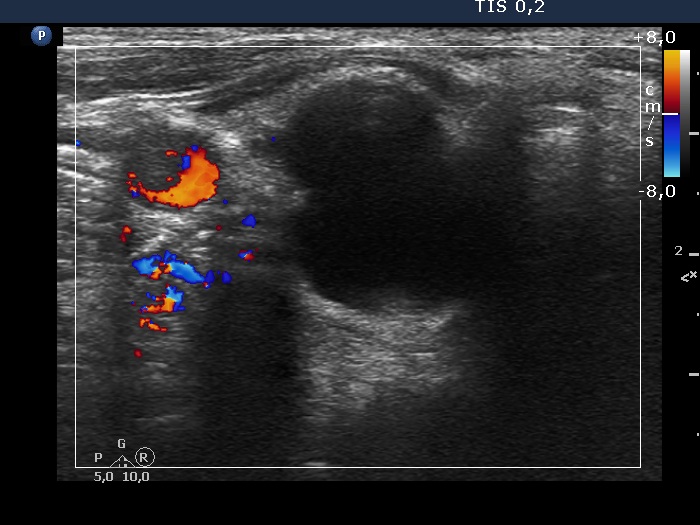

Ultrasonography. The thyroid was echonormal. There was an almost completely cyst in the right lobe. The left lobe was composed of a nodular area composed of multiple discrete lesions. The largest diameter of the nodular mass has increased from 15 mm to 37 mm in the last seven years. The size of the left lobe was 30x20x49 mm 7 years ago while the diameters were 39x23x58 mm at the present examination.

Additional tests: serum-parathormone 58.9 pg/mL (normal value 12-88), parathormone content of the aspirated fluid 2581 pg/mL.